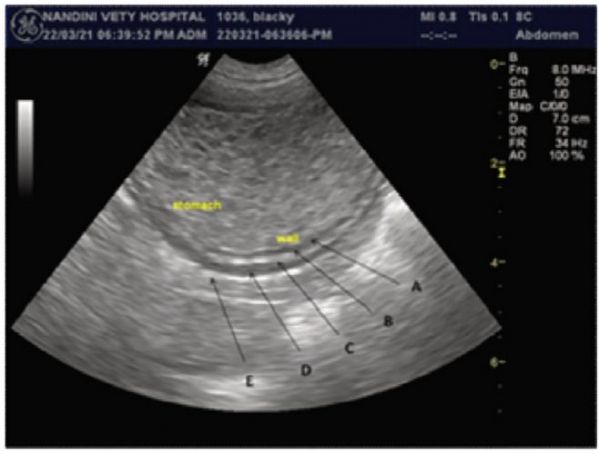

• 犬的胃粘膜下层较薄。食物物质和/或气体的存在会限制了犬胃的评估。狗的幽门-十二指肠交界处位于更外侧的位置。

图5 健康犬的胃壁超声图。胃壁有五层交替结构。从内到外,分别为 : 高回声粘膜表面(A)、低回声粘膜(B)、高回声粘膜下层(C)、低回声固有肌层(D)和高回声浆膜层(E)。